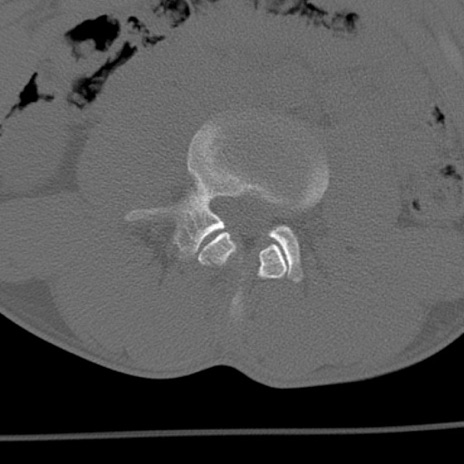

症例3 腰椎CT(横断像)

腰椎CT